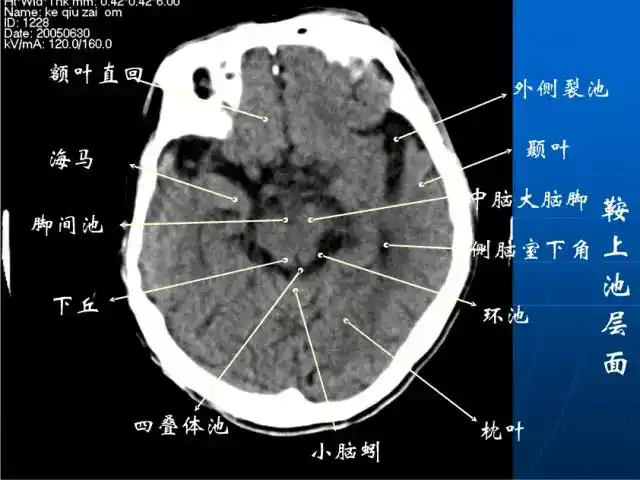

头部ct影像解剖

头颅ct解剖与常见出血梗死判读

详细标注版——颅脑ct正常解剖图谱_中央_小脑_纤维

解剖颅脑ct断层中英文对照干货满满

珍藏| 颅脑ct断面解剖彩色图谱